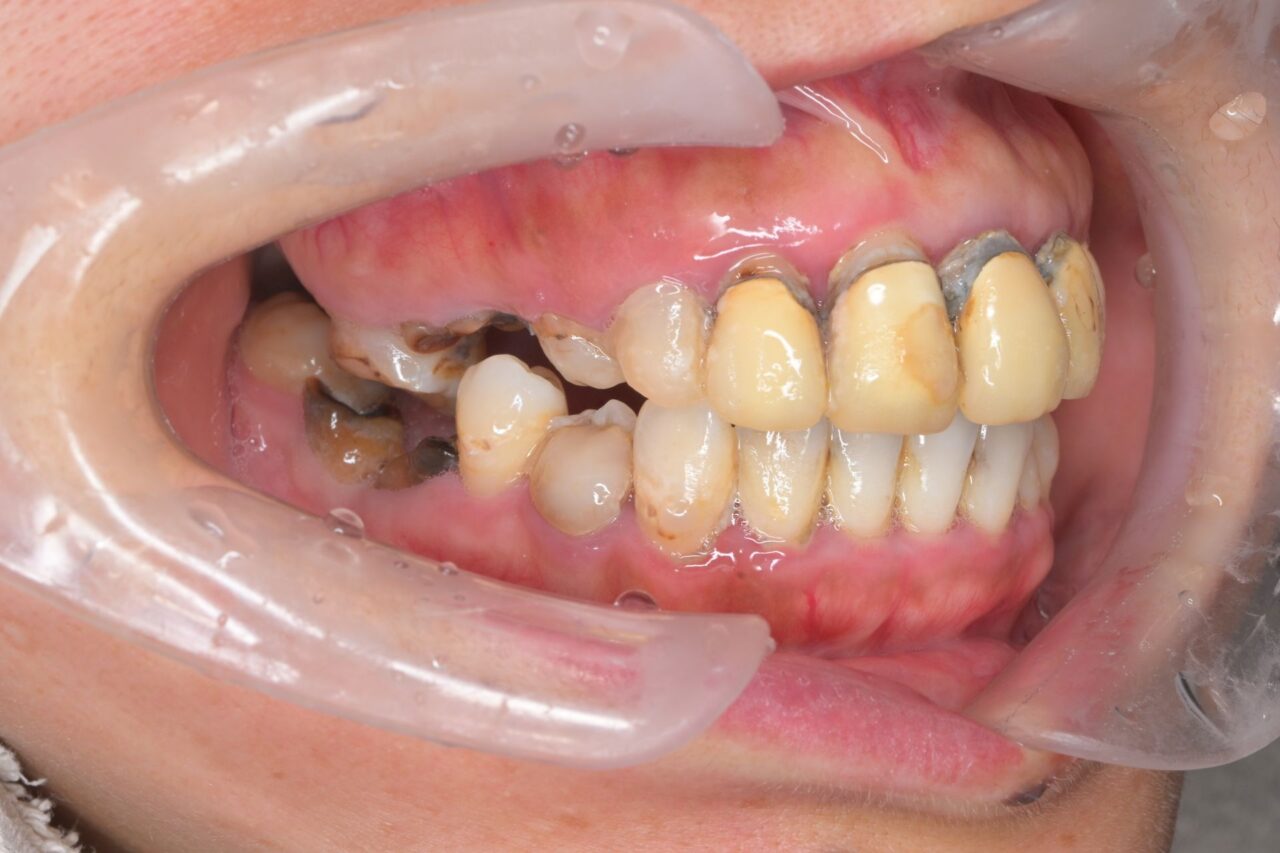

右側面

奥歯がありません。前歯があるので不格好にはならないのですが、奥歯=大黒柱が無い状態です。奥歯が無いことによって、かみ合わせが深くなってしまい、顎関節にも負担がかかっている状況です。